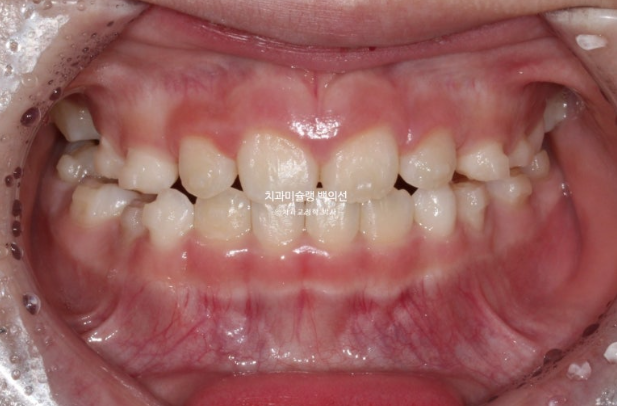

23.05

드디어 앞니 4개가 나왔으며 반대교합 치료 결과는 잘 유지되고 있습니다.

어금니 반대교합의 원인은 좁은 상악 악궁에 있습니다.

이제 인비절라인퍼스트 치료로 악궁확장, 앞니배열 등을 먼저 진행하여 교합간섭 해소를 도모합니다.

23년 6월부터 11월까지, 6개월간 첫세트 30개 장치를 모두 낀 후 모습입니다.

악궁확장을 통해 어금니 반대교합은 해소되었고 앞니배열은 좋아졌습니다.

나중에 영구치 송곳니 날 공간도 충분히 마련되었습니다.